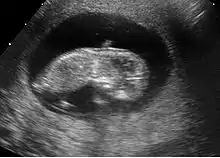

Embryon à 5 semaines

L'embryon est visible dès 5 semaines en cas d'utilisation de sonde endovaginale de haute fréquence. Il se présente comme une zone hyperéchogène coincée entre la vésicule vitelline et la paroi du sac ovulaire. Une activité cardiaque peut être visualisée. Il est déconseillé, à ce stade, d'utiliser le doppler pour entendre l'activité cardiaque embryonnaire en raison d'effet délétère possible sur la formation du cœur. En raison de la sensibilité humaine au mouvement, il est parfois possible de visualiser une activité cardiaque avant la visualisation de l'embryon. En pratique, l'activité cardiaque doit être systématiquement vue dès que l'embryon mesure 5 mm.